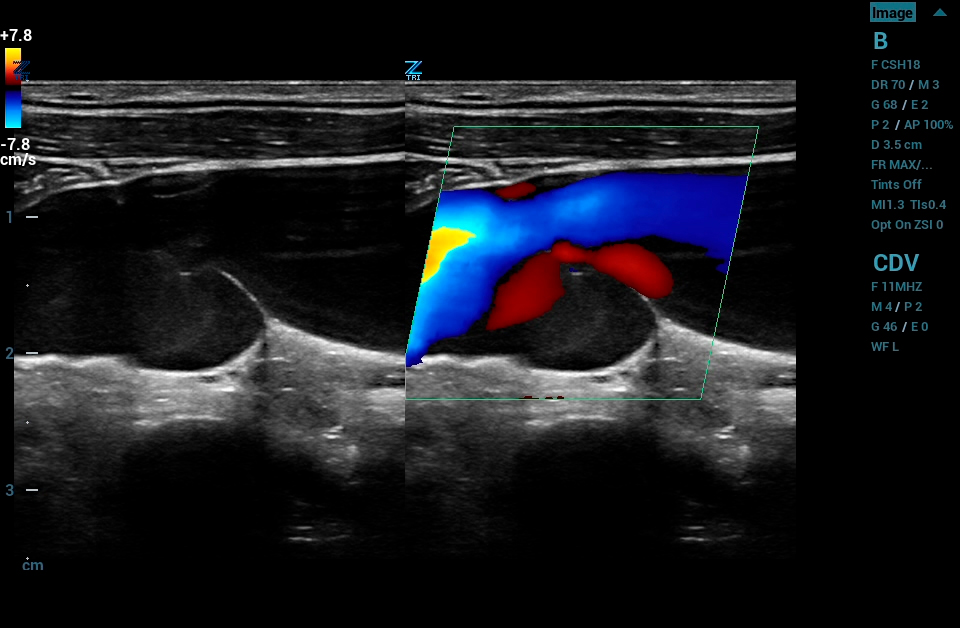

Contrast Enhanced Ultrasound (CEUS), Mindray’s unique approach to contrast imaging, allows clinicians to obtain the information needed with a lower dose of the contrast agent. CEUS is now available on all imaging transducers (1-20MHz).